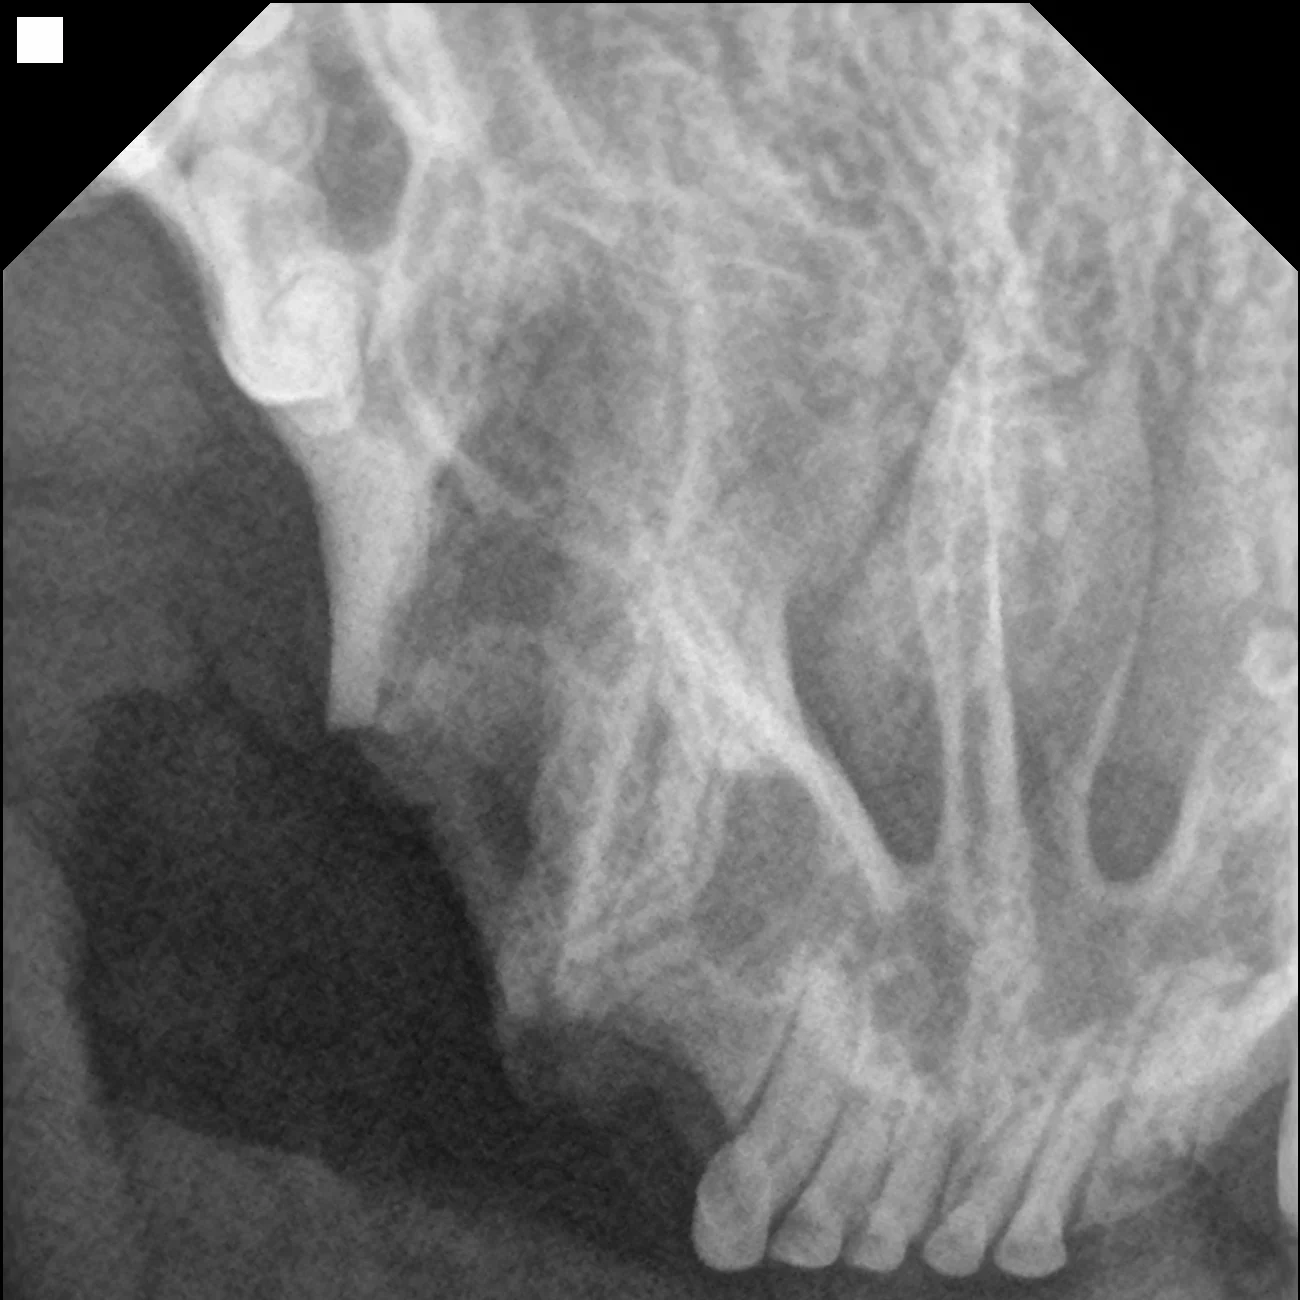

• 만성 구내염(feline chronic gingivostomatitis, FCGS)으로 목구멍염까지 확인되는 경우 통증 완화를 위해 전발치를 진행합니다.

• 뿌리를 남기지 않았는지 수술 전/후 치과방사선 촬영을 통해 확인합니다.

발치 전 치과 방사선